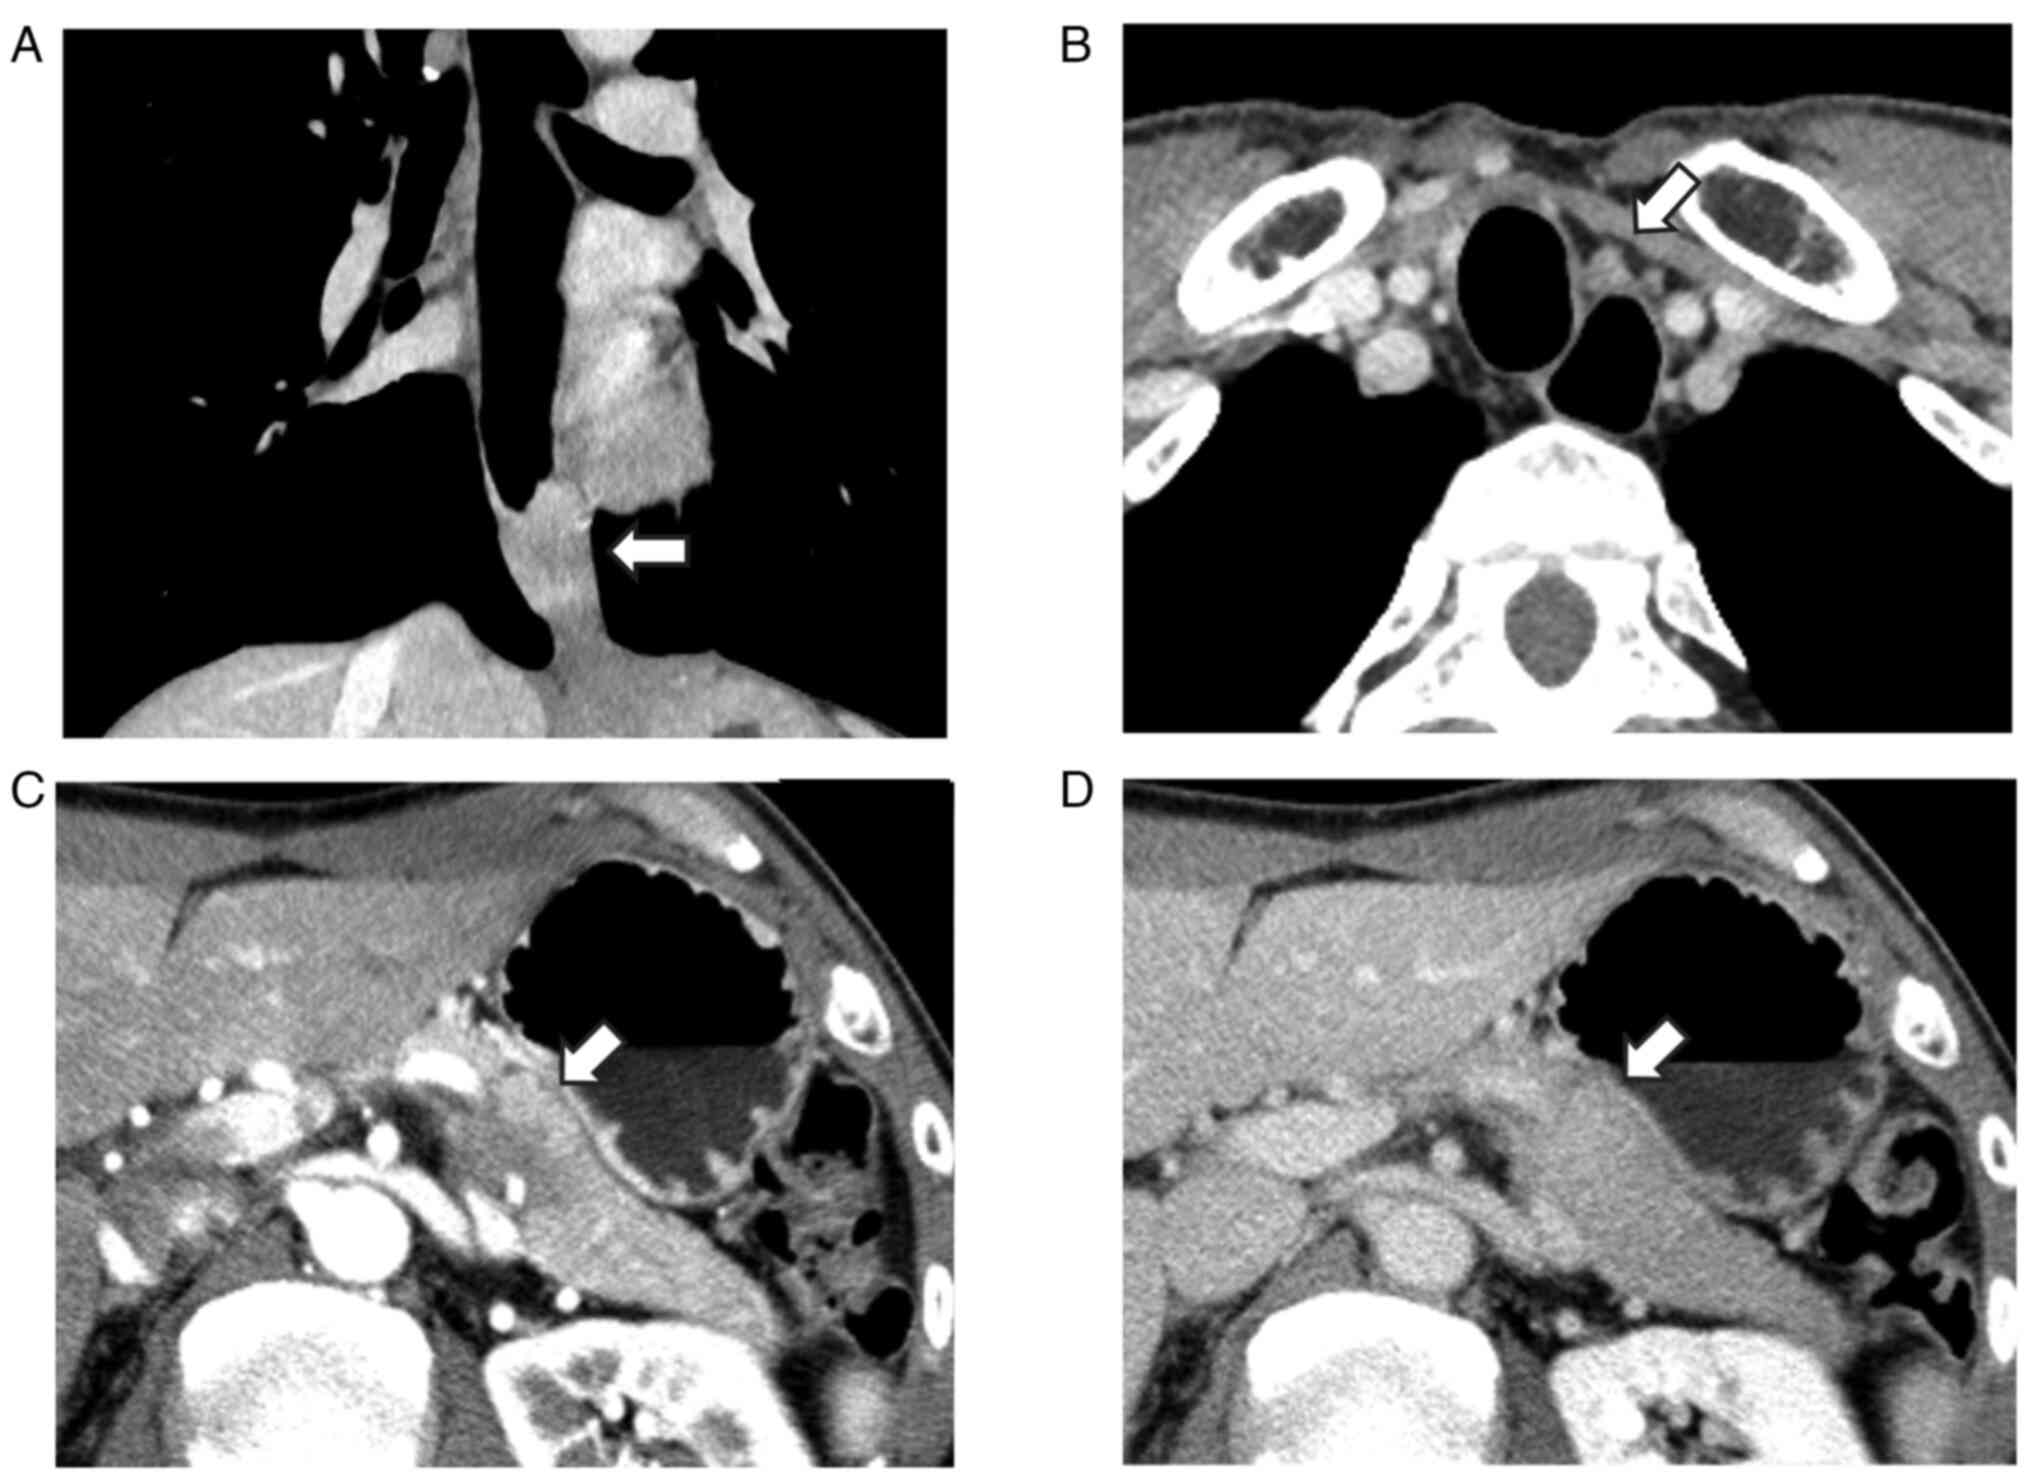

Figure 2

Contrast-enhanced computed tomography scan of the esophageal cancer. (A) Enlarged 106R lymph node, and (B) of the pancreatic tumor (indicated by the arrow), (C) in early phase and (D) in late phase. The pancreatic tumor exhibited gradual enhancement.

An esophagogastroduodenoscopy revealed a tumor that involved almost the entire circumference of the esophagus at a site 36 to 39 cm from the incisors (Fig. 1). An examination of a biopsy using an esophagogastroduodenoscopy revealed squamous cell carcinoma. Two pathologists were involved in this evaluation. Computed tomography revealed no obvious invasion of the surrounding esophageal cancer, and the 101R lymph node was enlarged (clinical T2N1M0, stage II; according to the eighth edition of the Union for International Cancer Control system) (14). A 22x20 mm-sized mass was also detected in the pancreatic tail. Contrast enhancement of the tumor was poor during the early phase and exhibited progressive enhancement (Fig. 2). The detected levels of tumor markers were as follows: i) carcinoembryonic antigen, 3.3 ng/ml (reference range, <4.1 ng/ml); ii) CA19-9, 2 U/ml (reference range, <37 U/ml); iii) squamous cell carcinoma antigen, 1.9 ng/ml (reference range, <2.5 ng/ml); iv) DUPAN-2, 25 U/ml (reference range, <150 U/ml), and v) Span-1, 6.8 U/ml (reference range, <30 U/ml). Due to esophageal stricture, an endoscopic ultrasound-guided fine needle aspiration biopsy (EUS-FNA) could not be performed, and the neoadjuvant therapy was not administered, since primary pancreatic cancer could not be excluded. Subsequently, it was decided that the patient should undergo a resection of both the primary cancer in the esophagus and the metastatic tumor in the pancreatic tail.